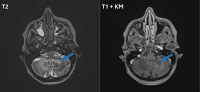

Abbildung 3: Patientin A: cMRT vom November 2023 (FLAIR-Sequenz, DWI-Sequenz, T1-Sequenz mit KM): Befundverschlechterung mit deutlicher Größenzunahme der Läsion links cerebellär mit peripherer Diffusionsrestriktion (blaue Pfeile), weiterhin keine Kontrastmittelaufnahme